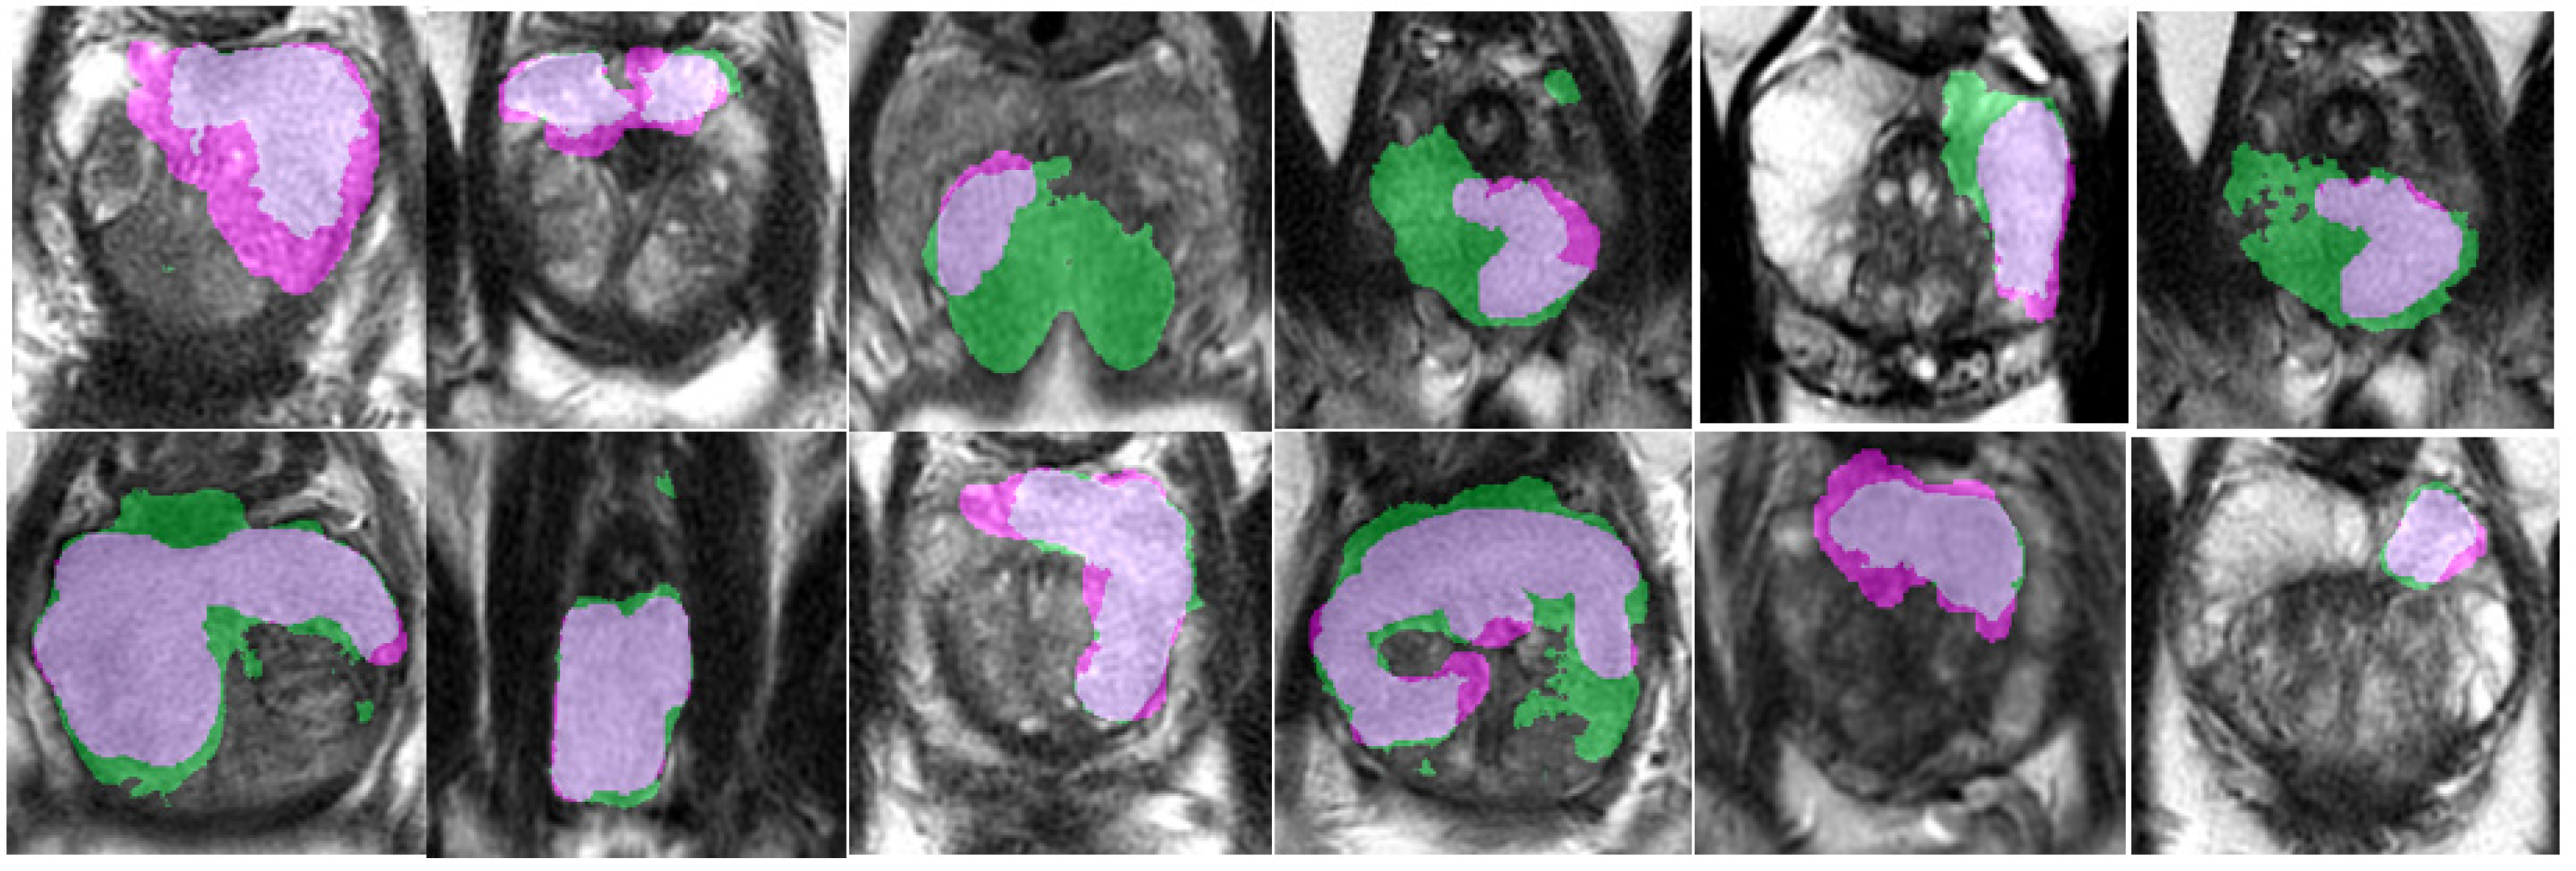

An example of segmentation of cancer foci by the final 3D cancer segmentation model is shown in Figure 18.

Figure 18. Segmentation of cancer by the final 3D segmentation model.